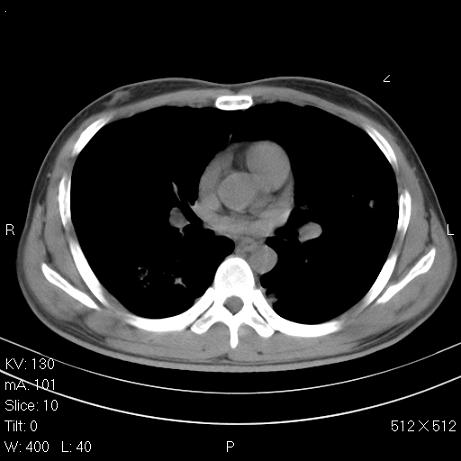

治疗后2周复查,请讨论

结合以前的ct片,还是考虑肺挫伤,吸收多了。

支持:创伤性湿肺。现肺挫裂伤(出血 积气)大部分吸收。建议继续治疗!

结合以前的ct片,支持创伤性湿肺。现大部分吸收。

支持:创伤性湿肺、肺挫裂伤。现肺挫裂伤(出血、渗出、液气腔)大部分吸收。建议继续治疗!

支持:创伤性湿肺、肺挫裂伤。现肺挫裂伤(出血、渗出、液气腔)大部分吸收.

结合老片支持创伤性湿肺、肺挫裂伤。

经治疗后病灶明显吸收,考虑创伤性湿肺、肺挫裂伤